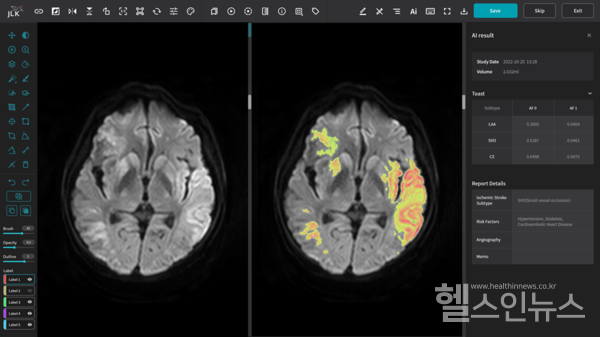

김범준 교수는 2005년부터 2022년까지 분당서울대병원의 입원 환자 6426명의 영상 데이터에 제이엘케이의 JBS-01K를 적용했다. 대상 기준은 최소 2번 이상의 MRI 촬영 이력이 있는 뇌경색 환자다.

연구 결과, JBS-01K는 뇌경색 부피를 정확하게 측정할 뿐 아니라, 추적 검사를 통한 뇌경색 부피의 변화양상을 정량적으로 분석했다. 본 연구에서는 25%의 환자에게서 일주일 이내 뇌경색 부피가 감소함을 최초 발견했으며, 뇌경색 부피 감소는 환자 예후와 밀접한 관련이 있다는 점을 밝혀냈다.

또한, 뇌경색 병변의 위치를 높은 정확도로 포착하고 정량적 분석이 가능한 JBS-01K의 임상적 유용성을 입증했다. 김 교수는 향후 뇌경색 환자의 급성기 치료 방침의 결정 및 예후 예측에 JBS-01K가 적극적으로 활용될 수 있음을 시사하고 있다고 전했다.